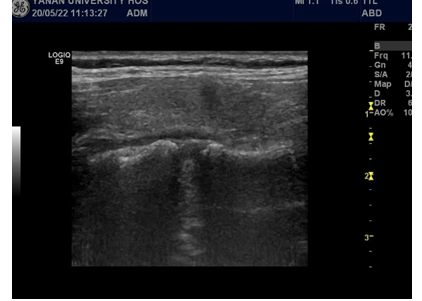

手术在超声医学科介入诊疗室完成。为了防止出现颈总动脉及喉返神经等重要组织损伤,我们在甲状腺周围注入生理盐水建立了隔离带,微波针进入病灶20s完成结节的消融。术后及时进行超声造影评估,甲状腺结节完全消失。

术后甲状腺结节情况